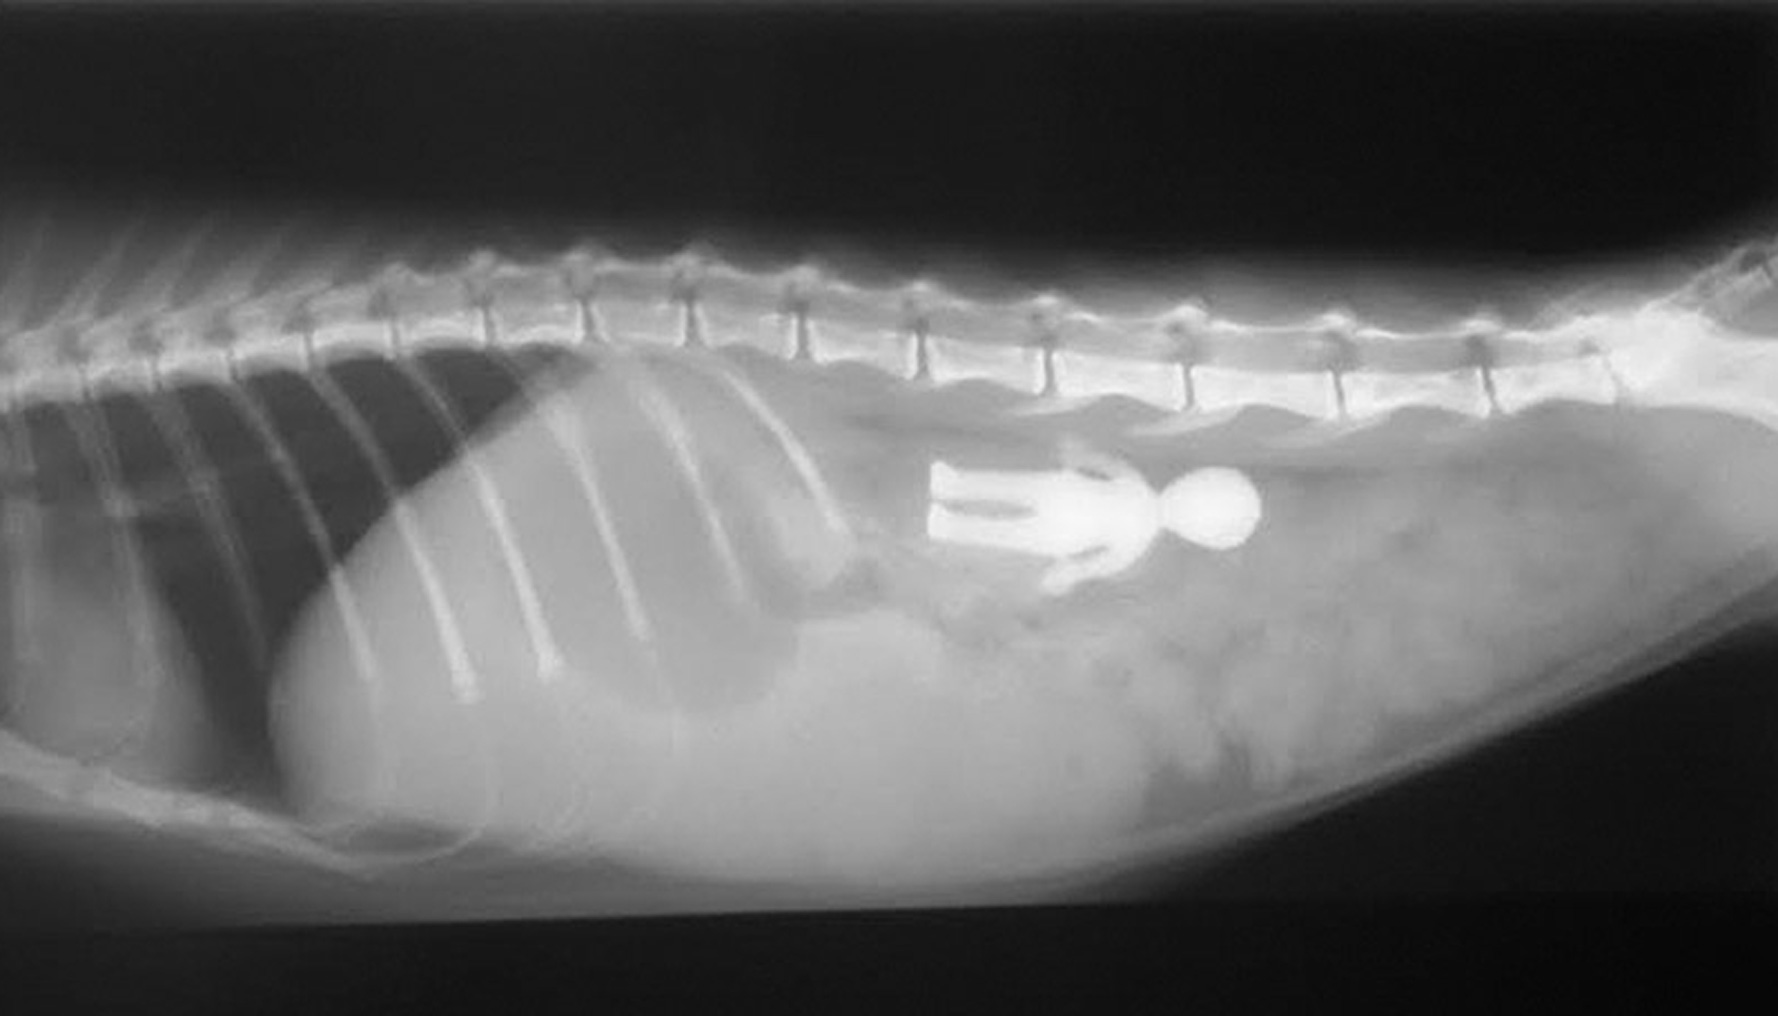

Foreign Body Removal

Options include inducing the pet to vomit, extracting the foreign body through the mouth using an endoscope, removing it surgically, or waiting to see if the object will pass through the pet's intestines naturally. “It is possible for a swallowed needle and thread to safely pass through the pet's intestines,”